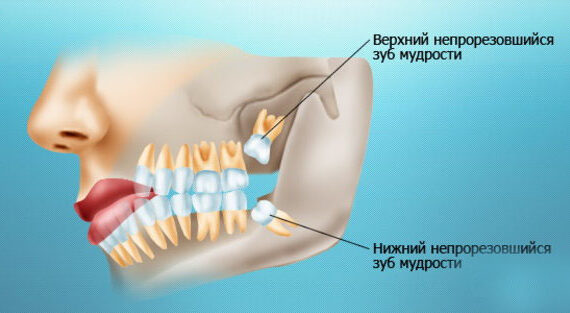

Что конкретно интересует вас в операции удаления зуба?

- Техника?

- Послеоперационные назначения и реабилитационный период?